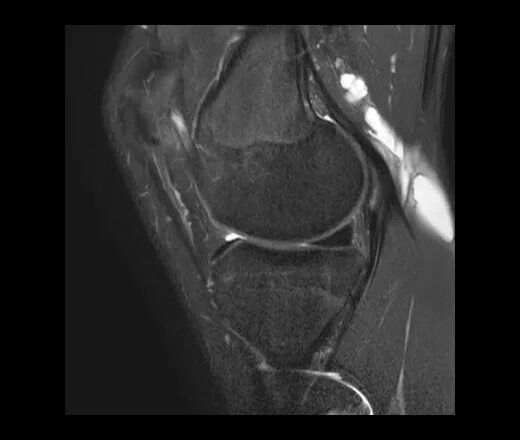

Мрт коленного сустава набережные